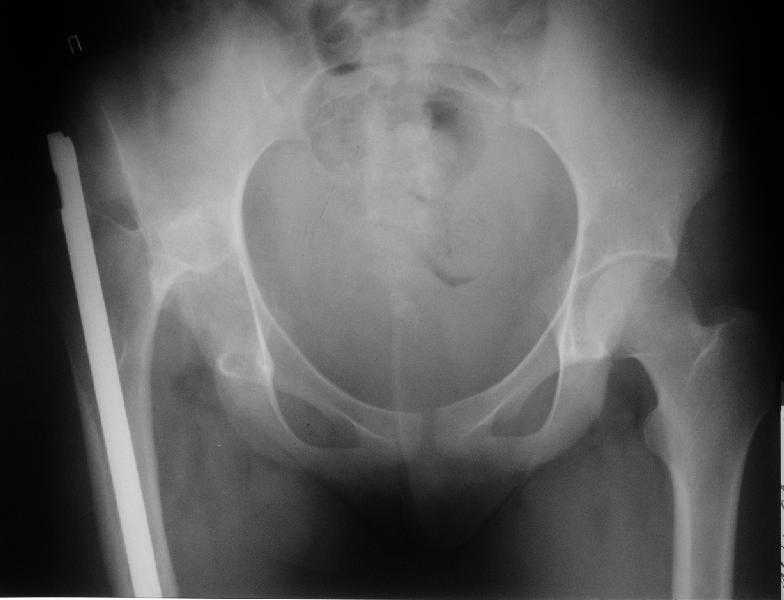

Застарелый вывих бедра

Здравствуйте уважаемые коллеги. Больная 18 лет. Травма 12.08.2007. Лечилась в одном из городов Свердловской области.

15.08.2007 в ЦРБ сделан открытый остеосинтез правого бедра интрамедуллярным стержнем, после чего была наложена гипсовая кокситная повязка и пациентка лечилась амбулаторно в течение 1,5 месяцев. На контрольном Rn исследовании в марте 2008 диагностирован подвздошный вывих правого бедра.

Поступила к нам в отделение. В отделении первым этапом был наложен аппарат внешней фиксации для низведения бедра. 30.09.08 интрамедуллярный стержень удален. Вторым этапом планируется эндопротезирование. В настоящее время у больной имеется контрактура коленного сустава, с амплитудой движений в пределах 30 градусов., и выраженный остеопороз вертлужной впадины и проксимального отдела бедра. Больныя пердвигается самостоятельно с опорой на здоровую ногу и костыли.

Какие проблемы при эндопротезиовании в этих условиях ожидать, и как с ними бороться? Еще и диафиз сросся не очень крепко, опасаемся, как бы не сломать. Очень выражен местный остеопороз, может быть, сделать все-таки цементный протез? Хотя 18 лет всего. Спасибо.